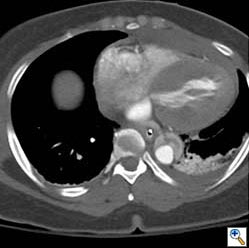

Figures 1b-d. Axial CT cuts demonstrating the dissection continuing into the left common iliac artery.

Figure 1e. Oblique sagittal CT reconstruction demonstrates the Type A dissection is complex with multiple fenestrations in the abdomen. Note bovine arch anatomy.

She was followed closely and a CTA was repeated at 3 months. This revealed minimal changes to the repaired aorta. However, at 6 months the follow-up CTA demonstrated an abrupt dilation of the descending aorta from 3.9cm to 6.5cm. (Figure 3) After extensive discussion, the patient returned to the operating room for a descending aortic replacement. Due to involvement of the distal arch, hypothermic circulatory arrest was utilized with an open proximal anastomosis just distal to the left subclavian artery origin down to T8 with a 26mm Gelweave graft (Vascutek Ltd). A lumbar drain was placed for spinal cord protection due to the distal extent of the repair. The false lumen pressurized at reperfusion, but would likely thrombose over time and was left alone. The patient recovered quickly and was discharged home on hospital day eleven with excellent impulse control.